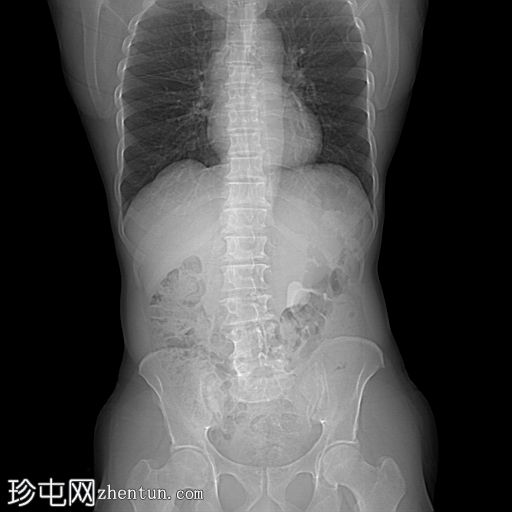

定位像

定位像显示:

左上腹象限可见一边界清晰的卵圆形不透光影

非增强CT KUB显示:

左肾盂内可见一高密度结石,压迫肾盂输尿管连接处。

下肾盏内可见一小结石

未见明显反流、肾盂肾盏扩张或肾周脂肪浸润

输尿管或膀胱内未见明显结石